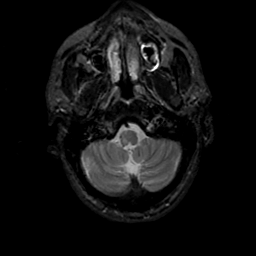

MR Study #19, August 25, 1991 -- Slice #6

Click on sagittal image to select slice. Click on thin tickmark to change timepoint, or thick tickmark for overlay.